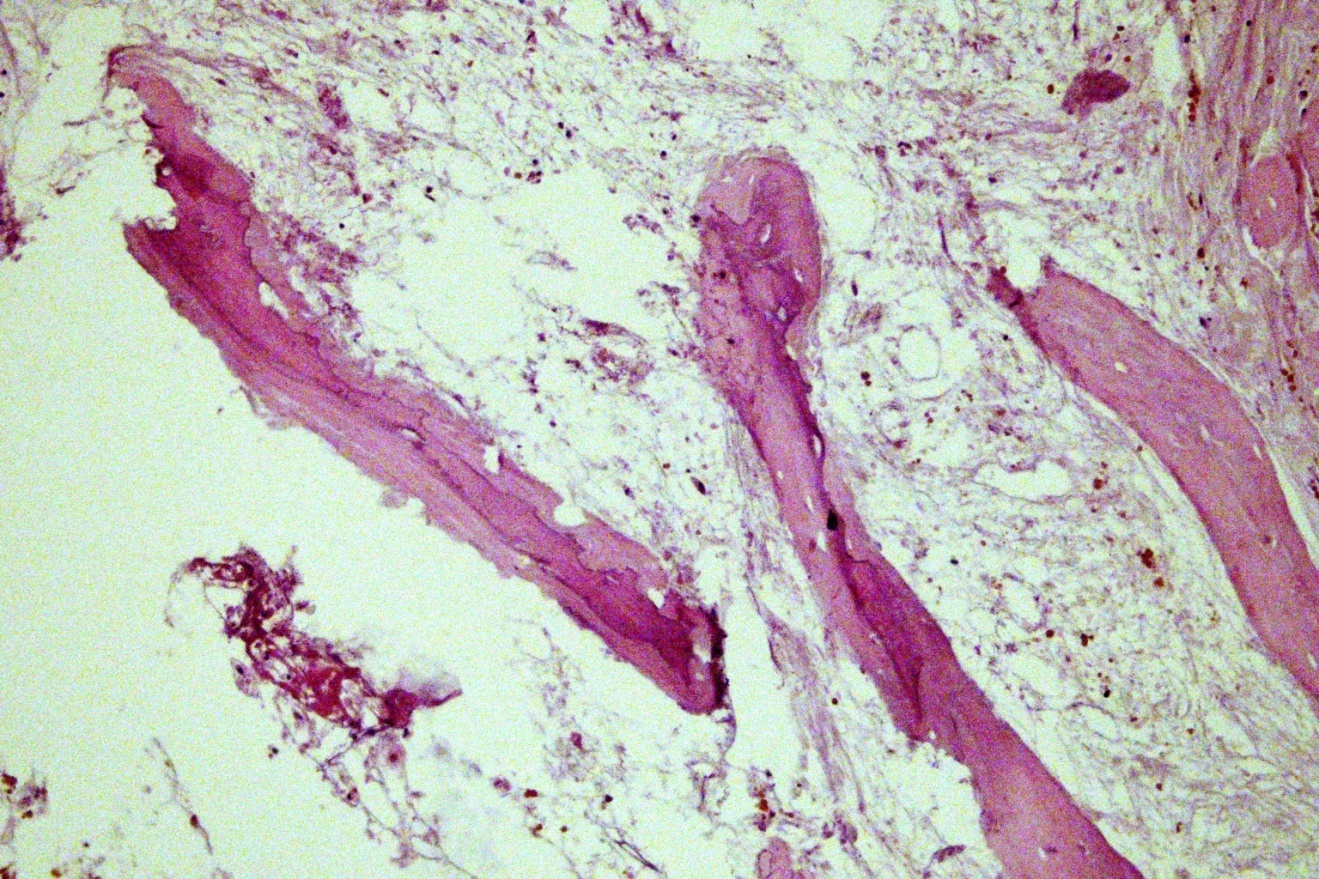

В результате патогистологического исследования фрагментов костной и мягких тканей, изъятых из зоны переломов, были выявлены морфологические признаки структурной дезорганизации костной ткани в зоне перелома, различные варианты репарации костной ткани, а также реактивные изменения со стороны окружающих мягких тканей. Структурная дезорганизация костной ткани проявлялась в недостаточной минерализации костной ткани, в деструкции костных балок с развитием очаговых признаков остеолиза. Так, на фоне признаков неравномерно выраженного отека, полнокровия и разволокнения основного вещества выявлялись признаки деструкции костной ткани с образованием очаговых скоплений мелких фрагментов разрушенных костных балок (рис. 1, а) и пазушного остеолиза с образованием полостей с неровными контурами в толще костной ткани (рис. 1, b).

Рис. 1. Деструктивные изменения костной ткани в зоне перипротезных переломов бедренного компонента: а — разрушенные костные балки с очаговыми скоплениями мелких костных обломков; b — пазушный остеолиз в зоне оссификации хрящевой ткани. Окраска гематоксилином и эозином. Увел. ×160

Fig. 1. Destructive changes in periprosthetic fractures bone tissue of the femoral component: a — destroyed bone beams with focal accumulations of small bone fragments; b — axillary osteolysis in cartilage ossification fabrics. Staining with hematoxylin and eosin. Magnification × 160